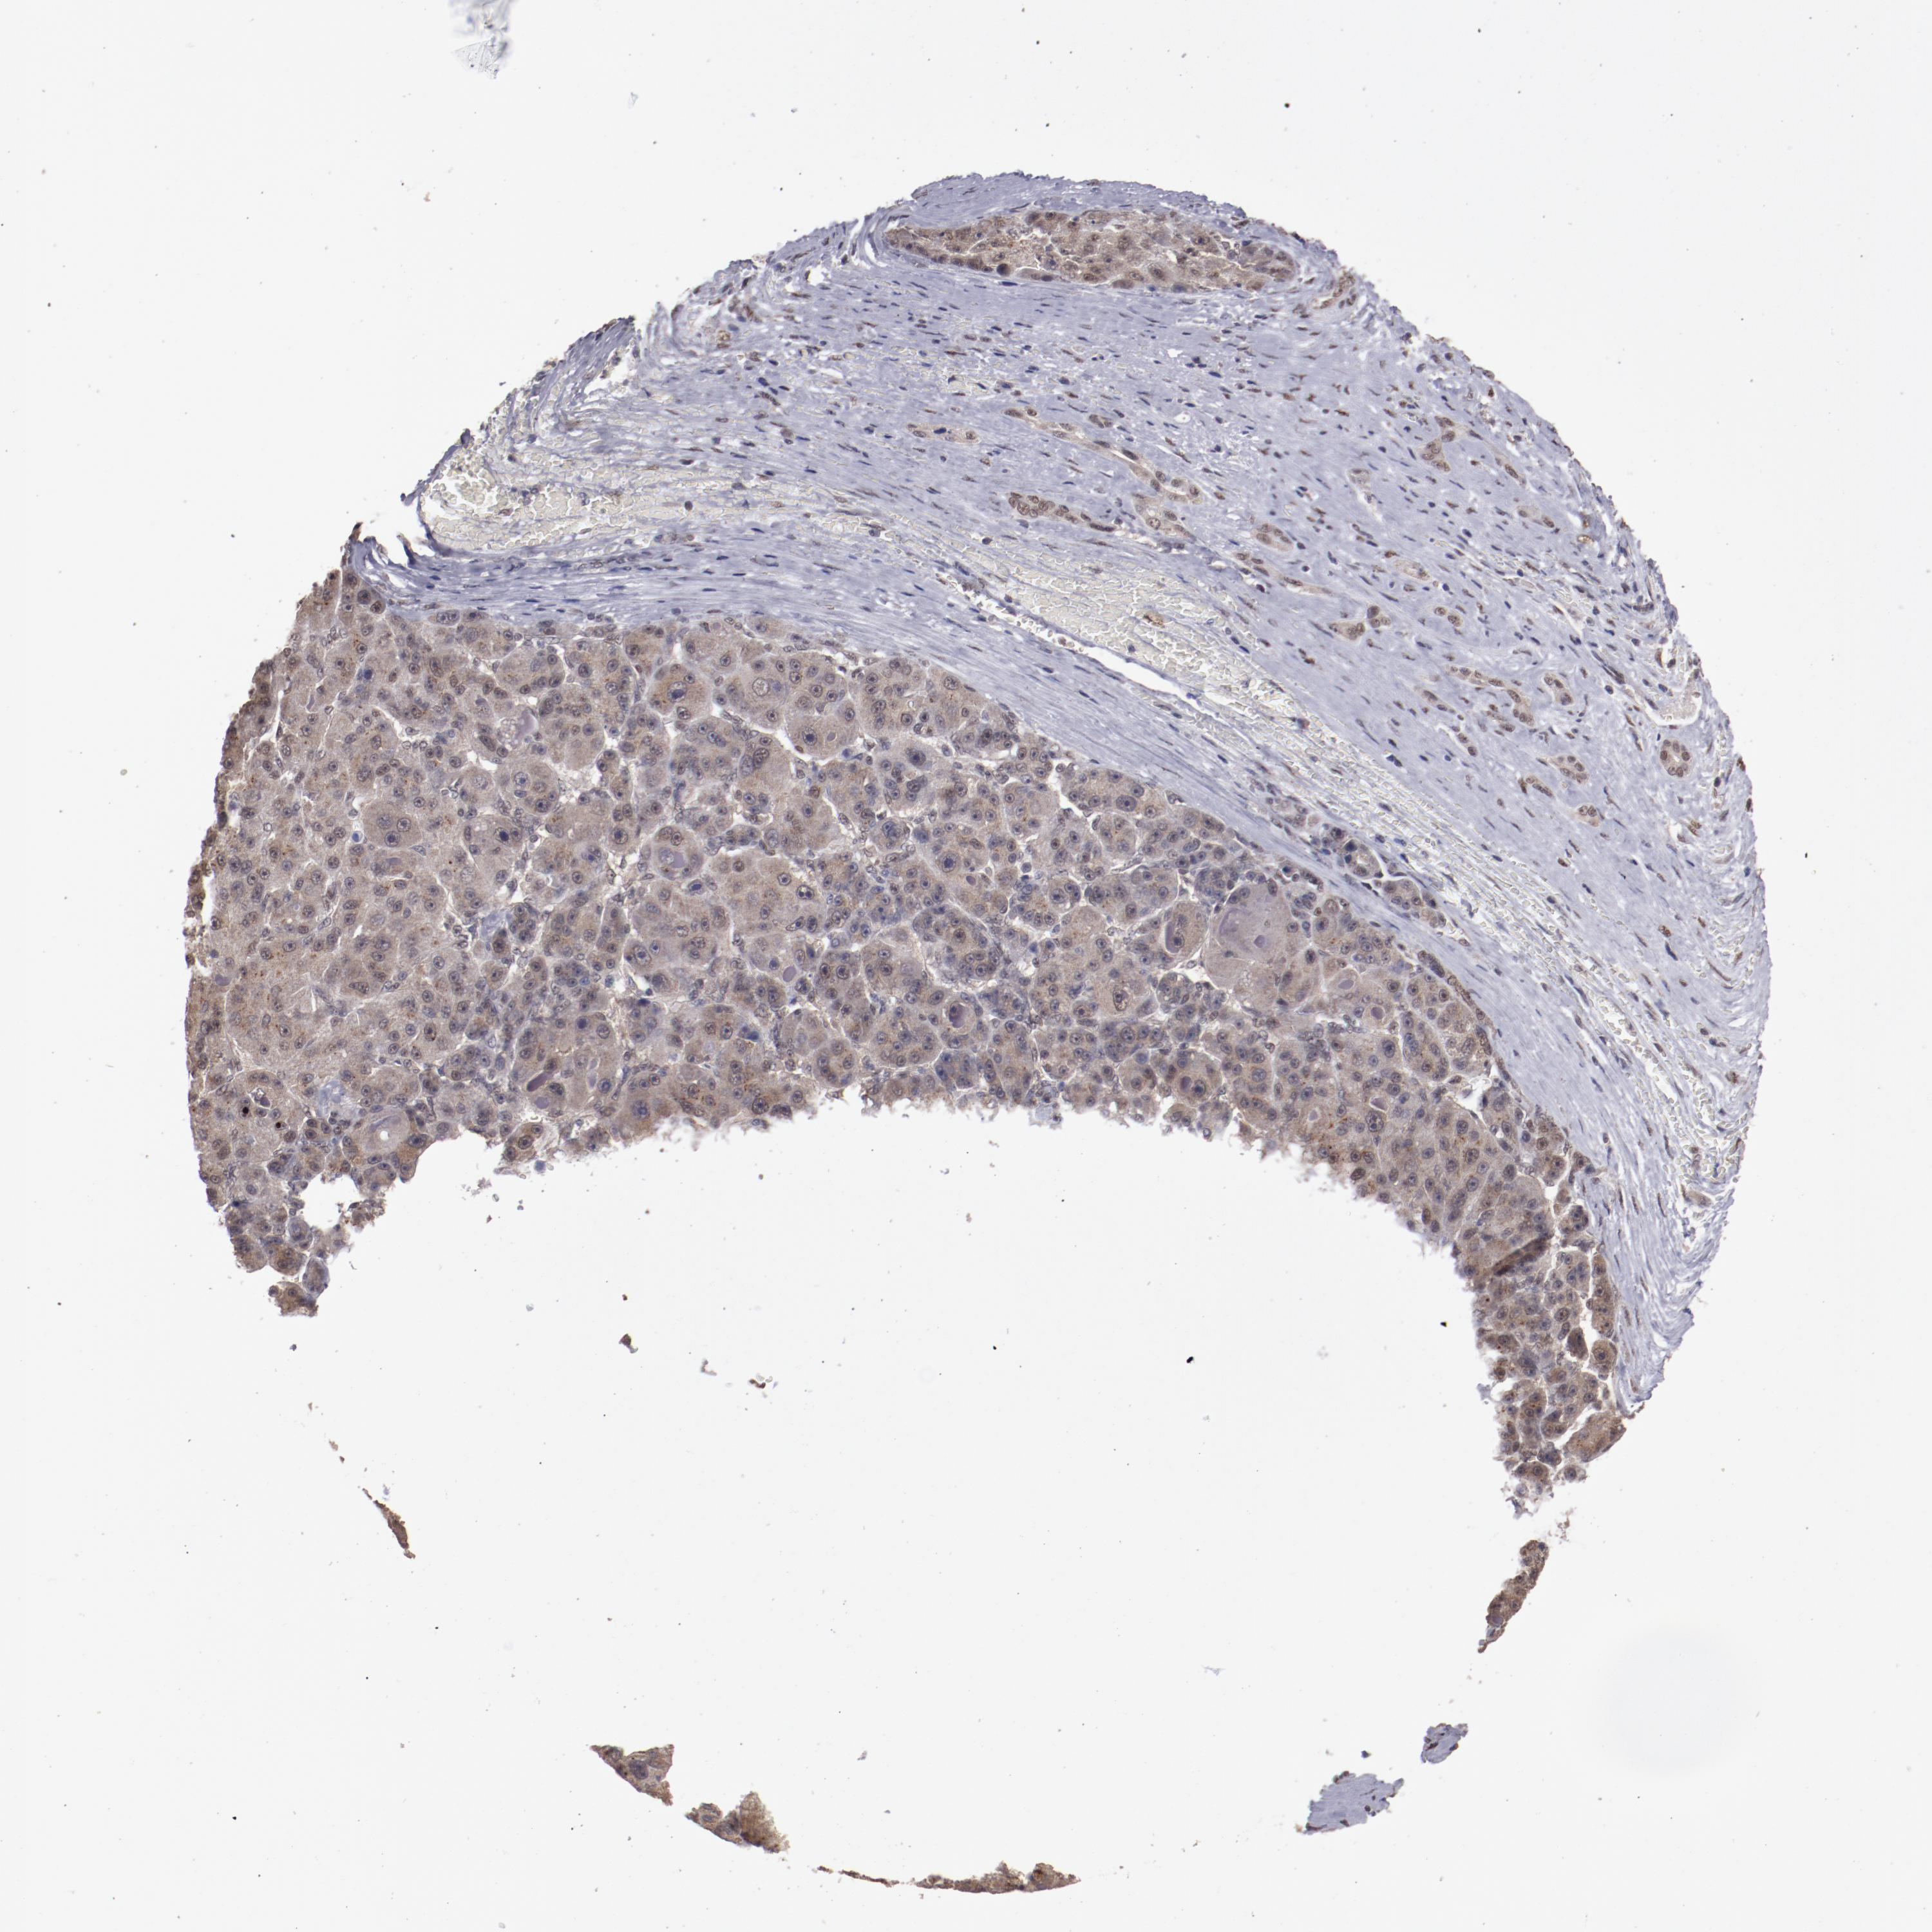

LIVER CANCER - Protein expressioni

A mouse-over function shows sample information and annotation data. Click on an image to view it in a full screen mode. Samples can be filtered based on level of antibody staining by selecting one or several of the following categories: high, medium, low and not detected. The assay and annotation is described here.

Antibody stainingi

Antibody staining in the annotated cell types in the current human tissue is reported as not detected, low, medium, or high, based on conventional immunohistochemistry profiling in selected tissues. This score is based on the combination of the staining intensity and fraction of stained cells.

Each image is clickable and will lead to virtual microscopy that enables deeper exploration of all samples and also displays staining intensity scores, fraction scores and subcellular localization as well as patient and tissue information for each sample.

Antibody HPA001759

Antibody CAB004318

Staining

High

Medium

Low

Not detected

Intensity

Strong

Moderate

Weak

Negative

Quantity

>75%

75%-25%

<25%

None

Location

Nuclear

Cytoplasmic/membranous

Cytoplasmic/membranous,nuclear

Cholangiocarcinoma

Carcinoma, Hepatocellular, NOS